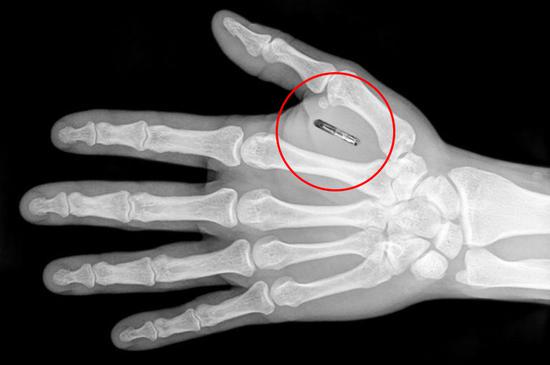

现在有了这种芯片,她只需要在手腕上贴个贴片就能完成所有操作。看到那贴片时,我感到有些不安,因为它与科幻电影中的植入式芯片越来越相似了。实际上,瑞典早在五年前就开始试验类似技术,当时有一个叫"Digital ID"的项目,计划在市民的耳后植入微型芯片,用来存储身份证号、医疗记录等信息。项目启动时,政府宣称这是"数字时代的身份证",声称比传统证件更安全。

实施后问题接连不断。有位程序员在技术论坛吐槽,每次去超市都要让店员用设备读取芯片,这和在公共场所出示身份证有什么区别。我觉得这种技术在某些场景确实挺方便。上周在斯德哥尔摩医院,护士用手机扫我的芯片,瞬间调出所有病历。不用排队不用翻文件,整个过程不到一分钟。